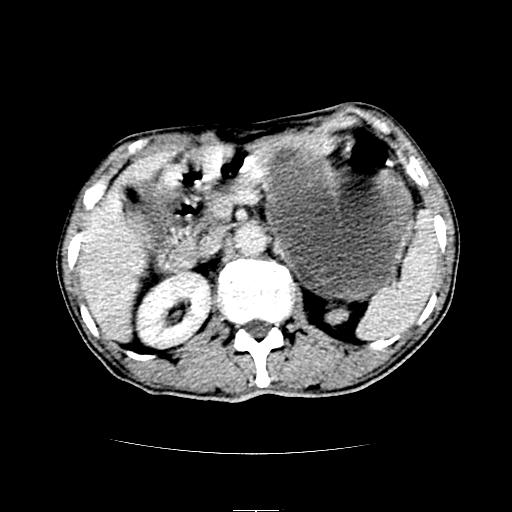

左上腹胃、脾及胰腺间巨大囊性占位性病变,内见多数薄隔,有轻度强化,明显占位效应。左肾见一小囊肿。

考虑:1、左上腹巨大囊肿(可能来源于胰腺)。

2、左肾小囊肿。

左上腹胃、脾及胰腺间巨大囊性占位性病变,内见多数薄隔,有轻度强化,明显占位效应,胰腺及左肾结构清楚,明显向后下方推压 移位。左肾见一小囊肿.多考虑:1 网膜巨大囊肿。2 左肾小囊肿。

1胃脾胰之间一巨大囊性影,胃明显向前推移,胰体尾部似肥大,考虑囊性影来源于胰腺(假性囊肿?)2左肾小囊肿。

考虑胰腺巨大囊肿,左肾低密度灶从形态和强化方式看不象囊肿,应考虑肿瘤。

左上腹胃、脾及胰腺间巨大囊性占位性病变,其内见多数薄隔,有轻度强化,明显占位效应。左肾见一小囊性变。

左肾囊肿;网膜巨大囊肿。